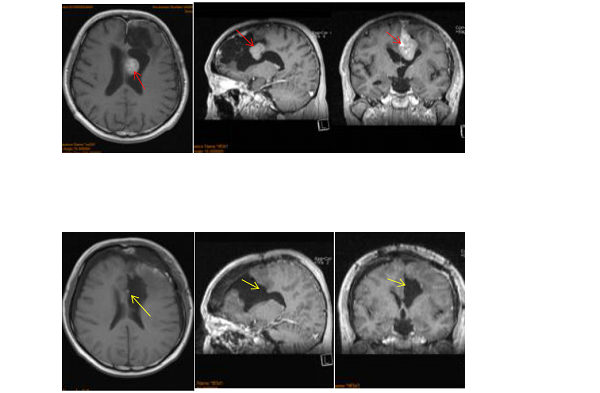

李阿姨的多发脑膜瘤就是长在大脑左侧凸面及大脑镰旁,这些不同部位毗邻大脑的诸多功能区和神经血管,手术全切难度之大,风险之高,令众多神经外科望而却步。这也正是他在国内只做了部分切除以及肿瘤很快复发的主要原因。

针对李阿姨的情况,巴特朗菲教授取患者仰卧位、前额部冠状切口、左侧为主。右侧额骨骨瓣过矢状窦,完全暴露矢状窦前1/3,及部分右侧额部硬脑膜。完全切除全部肿瘤,扩大切除左额硬脑膜,到达正常厚度硬脑膜为止。全切前段大脑镰,切除前1/3上矢状窦及下矢状窦。受累颅骨的内板以磨钻磨除后复位。手术实现脑膜瘤Simpson 0级切除,地保护了正常的脑组织结构,展现了其国际水准的技术水平和教授风采。